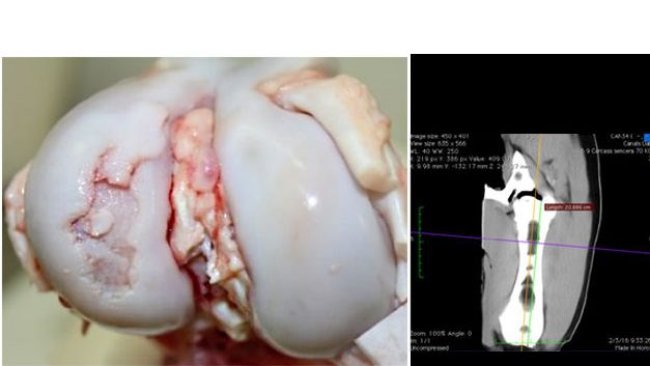

Lameness and nutrition

This article reviews the effect of components of the diet on the bones and osteochondrosis, this being the main caused of lameness and a reason for the culling of young sows. Therefore, they are important concepts to bear in mind in the diets for the rearing of gilts.